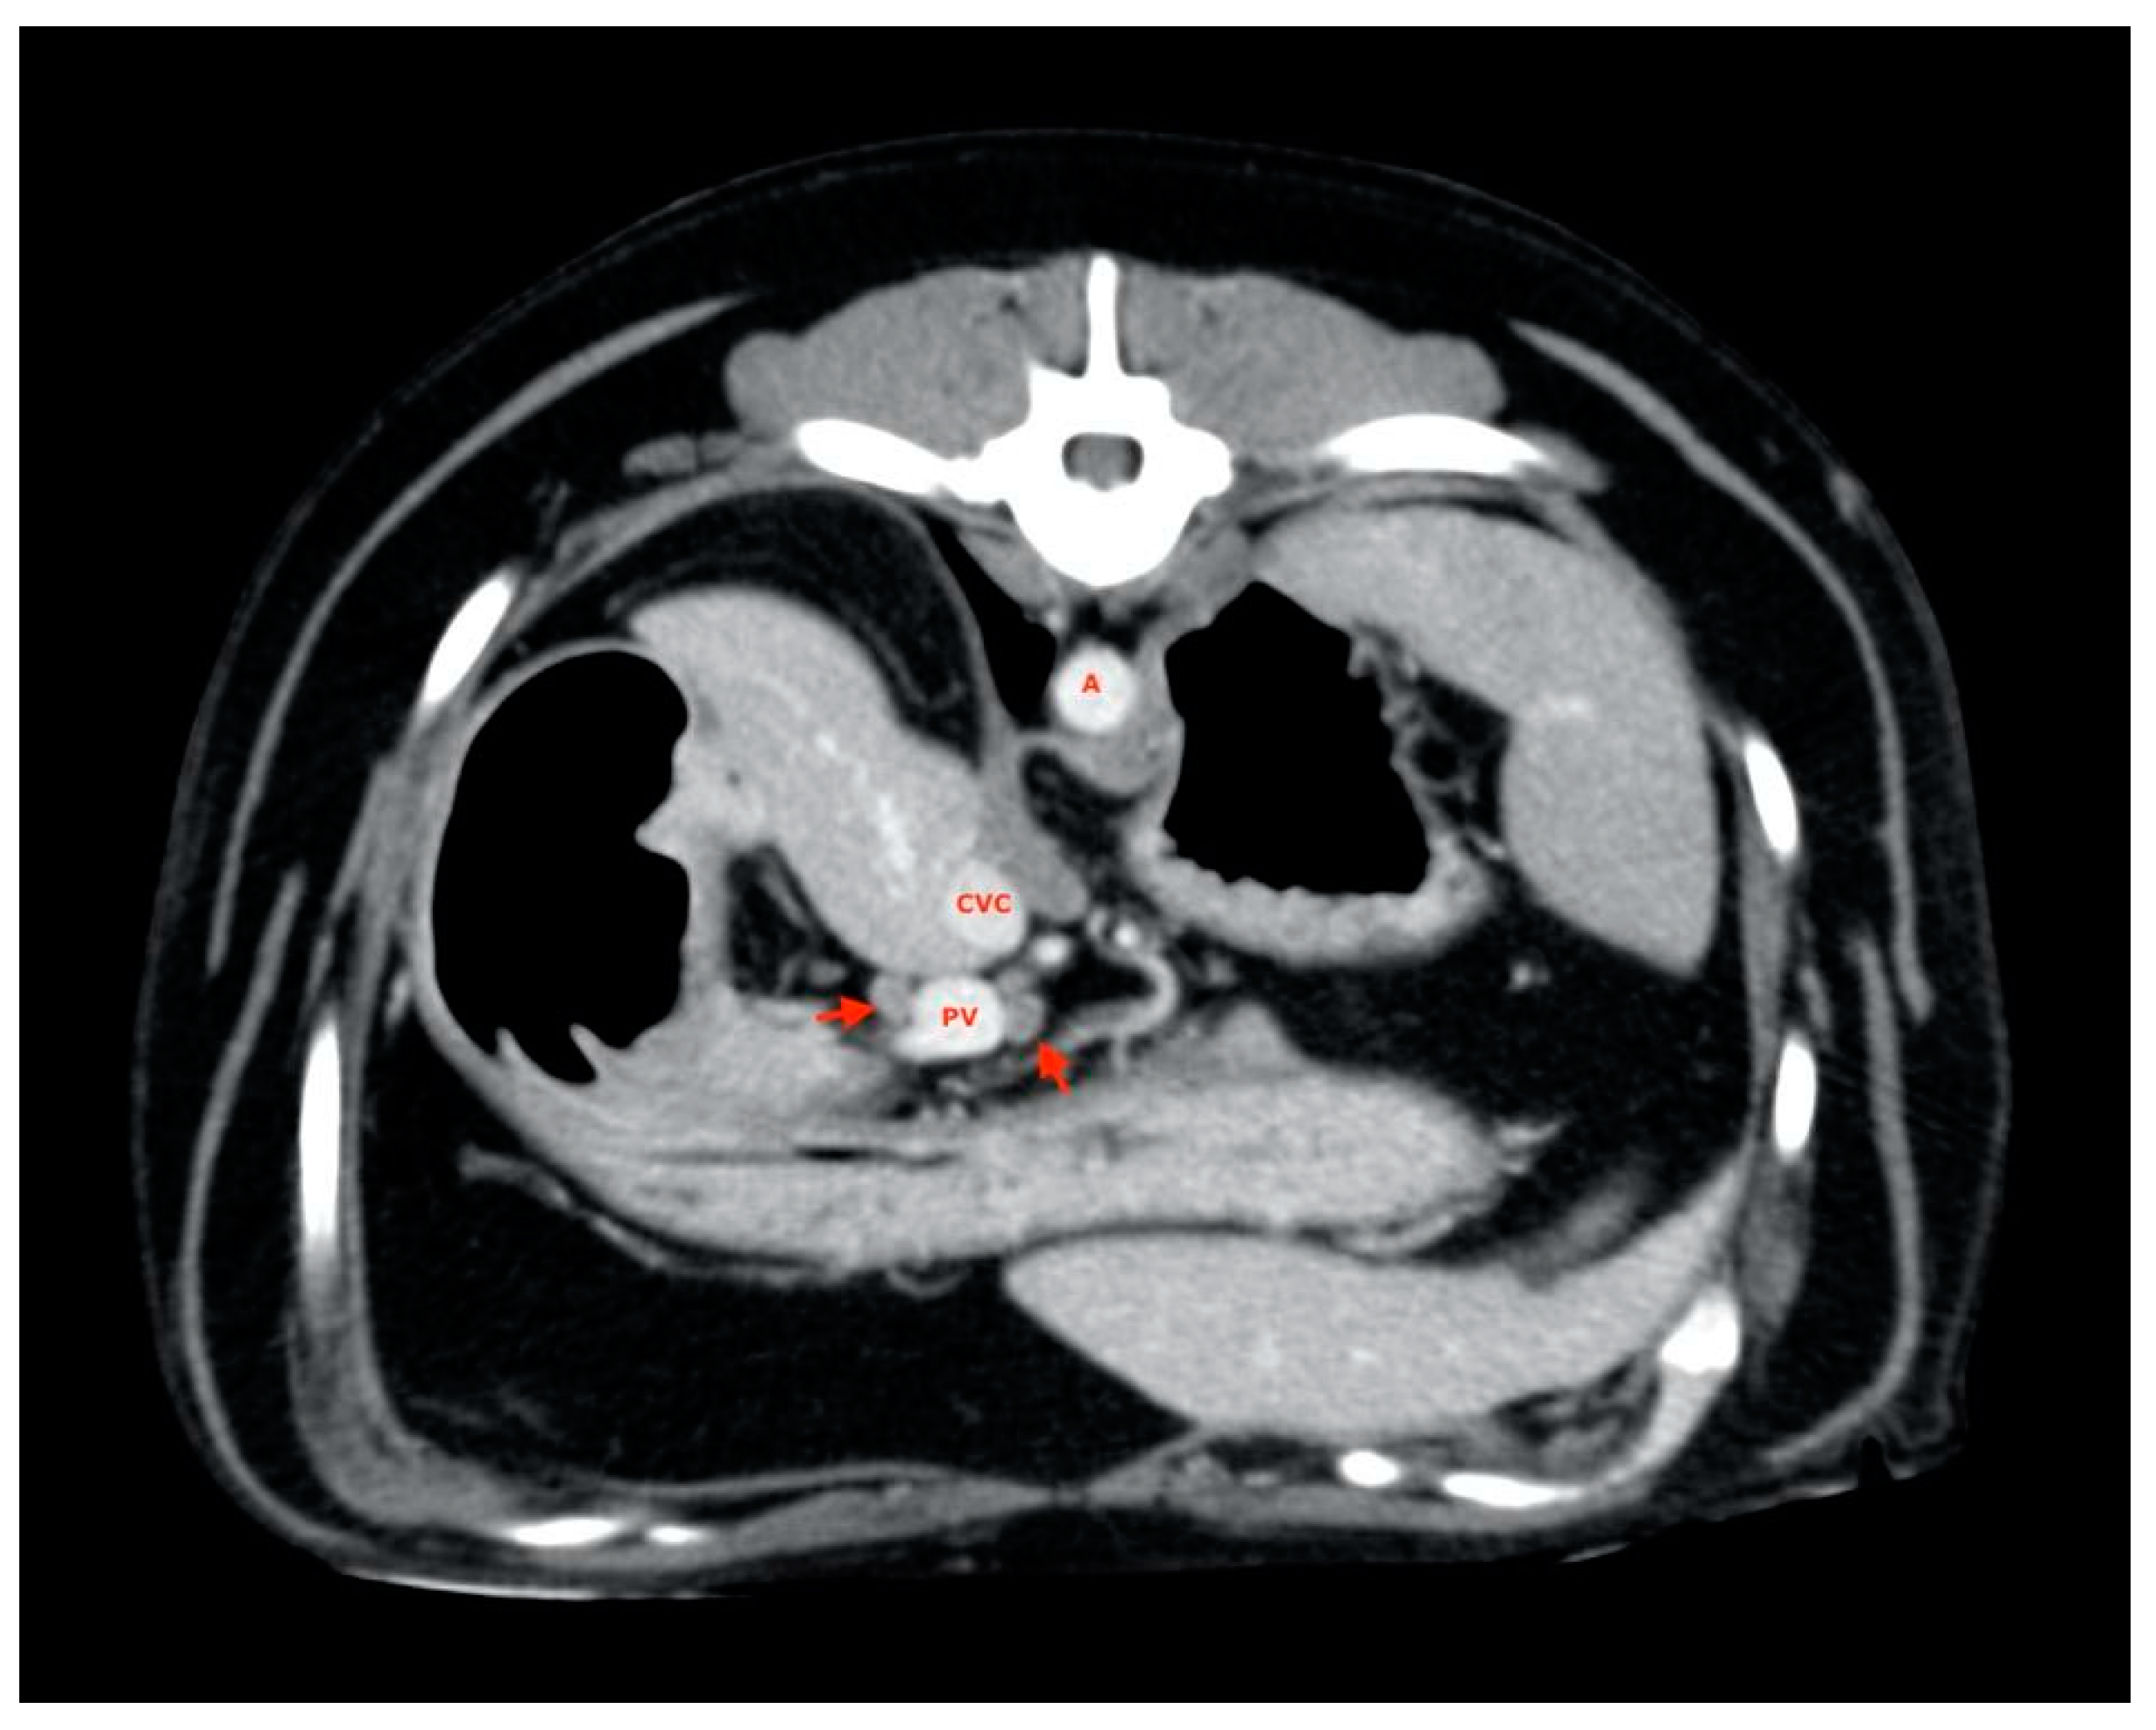

2.5. Measurements